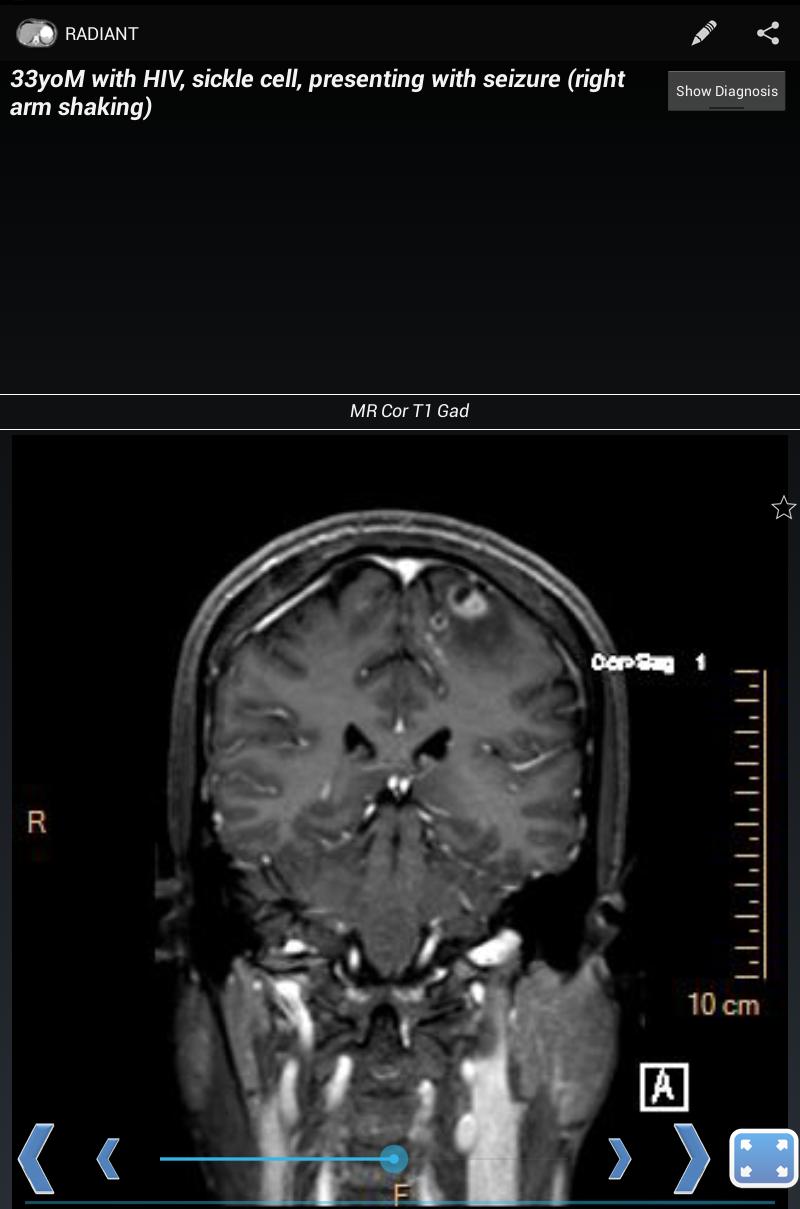

Com o Radiant, você pode criar casos mostrando raios-X, ultrassom, CT, ressonância magnética ou qualquer outra modalidade de imagem. É uma ótima maneira de aprender radiografias de tórax, anatomia normal e processos de doenças comuns, usando imagens médicas de diagnóstico reais e de alta qualidade.